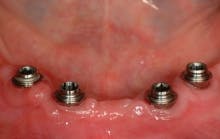

All-on-4 advocates claim that this type of treatment plan reduces cost and saves treatment time, but with the introduction of the ScrewIndirect one-piece implant that provides the implant, abutment, comfort cap, and transfer at a fraction of the cost of the implant alone from all the major implant companies, the economics argument for using the minimum number of implants is no longer valid. The ScrewIndirect screw-receiving platform allows splinting of implants that have up to 40 degree divergence, allowing distal angulations of up to 20 degrees if desired. Placement of five implants in the lower symphysis and six anterior to the maxillary sinuses can be relatively straight and still support adequate length of distal cantilevers. Four ScrewIndirect implants can also be placed, as shown below, splinted with a distal attachment for retention of an overdenture, but providing the patient with a fixed-detachable prosthesis that eliminates the need for a removable prosthesis is a more natural solution to restoring an edentulous jaw.

The ScrewIndirect one-piece implant offers a 3.0 mm D implant with adequate strength. All four diameter options (3.0 mm, 3.7 mm, 4.7 mm and 5.7 mm) have the same 5 mm D multi-unit platform. The 3.0 mm D implant allows treatment of narrow ridges and simplifies accurate placement during flapless surgery. Providing teeth in one day to edentulous patients and immediate implant placement following extractions is becoming the treatment of choice. The patient's existing denture is converted to a fixed-detachable prosthesis immediately following implant placement. This is accomplished by attaching titanium sleeves to the implants that project through holes cut in the denture and attached them to the denture with cold-cure acrylic followed by shortening the denture flanges.